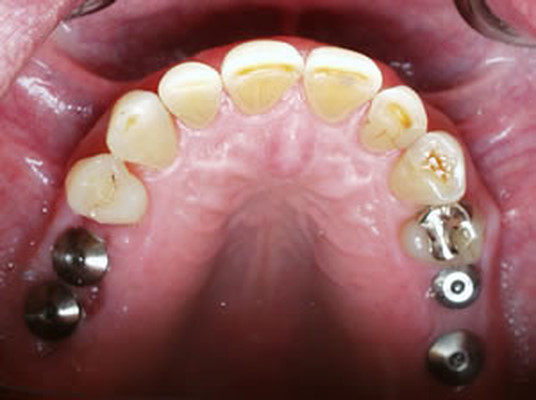

▶ 상악과 하악의 명확한 교합을 위해 적정한 각도로 임플란트를 식립하여 정교하고 강도 높은 보철 제작으로 실제 사용 시 불편함을 제거합니다.

음식을 씹을 때 흔들리거나 이물감이 들지 않도록 임플란트가 뼈와 강하게 결합되는 것이 중요한데요. 이는 임플란트의 수명과 직결되는 요소로 친수성이 높은 칼슘 임플란트를 사용하여 임플란트와 치조골간 골 생성이 치밀하고 우수하여 강한 골 결합력을 유지하도록 해야 합니다.

오스템 임플란트 CA, BA 제품 및 오스템 A-Oss, 오스템 Ossguide를 통해 만족도 높은 결과를 확인하실 수 있습니다.